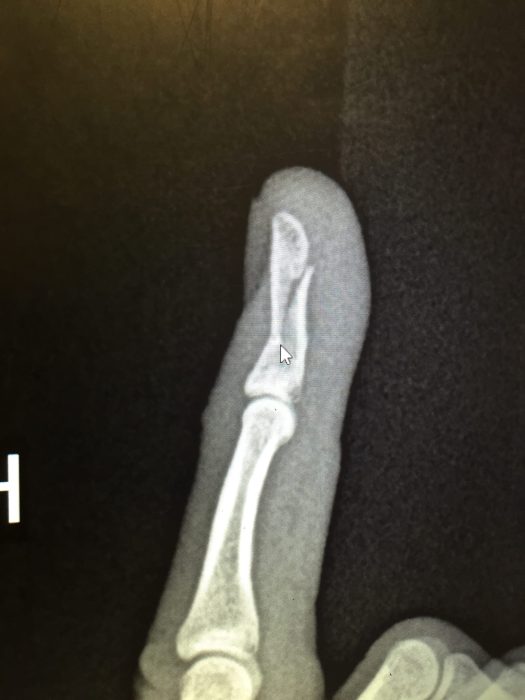

We finished in roughly an hour. As the youngest finisher, Josh got an honorable mention at the awards ceremony. I joked that he won his age group, and we asked a fellow racer to take a picture showing how we both felt: